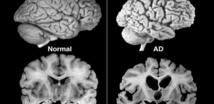

Cuando el cerebro no funciona correctamente, esa proteína se acumula de forma anormal en algunas partes, lo que lleva a degeneraciones neuronales tales como la enfermedad de Alzheimer, la forma más común de demencia.

Pero, un pequeño grupo de unos cien pacientes que tomaron el fármaco experimental sin ningún otro tratamiento adicional mostró un ritmo de atrofia cerebral muy lento, según los resultados del estudio presentado el miércoles en la Conferencia de la Asociación Internacional de Alzheimer, reunida en Toronto.